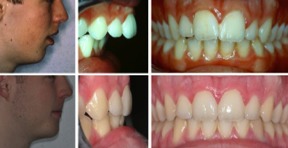

Fall 5: Vergrösserter Überbiss und Tiefbiss

Therapie: Extraktion von zwei Zähnen im Oberkiefer sowie Gartenhag